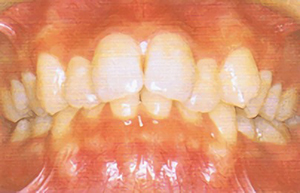

type04

• 噛み合わせると前歯が深く沈み、上の歯が下の歯を隠してしまう

「過蓋咬合(かがいこうごう)/ディープバイト」である可能性があります。噛み合わせが深すぎる状態です。乳歯の早期喪失や、顔面骨格の不調和が原因です。笑ったときに上顎の歯肉が見えてしまったり、下の前歯が上顎の内側の歯肉を傷つけて炎症を起こすことがあります。